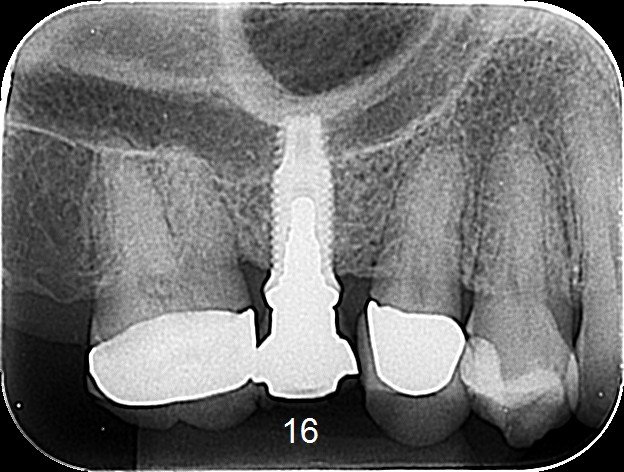

Hola a todos, necesito saber que implantes es el que está en posición de diente 2.4, adjunto la RX del implante con la rehabilitación instalada, y luego una foto intra-oral [...]

Buenas, necesito saber que implante es este para rehabilitarlo. Gracias de antemano